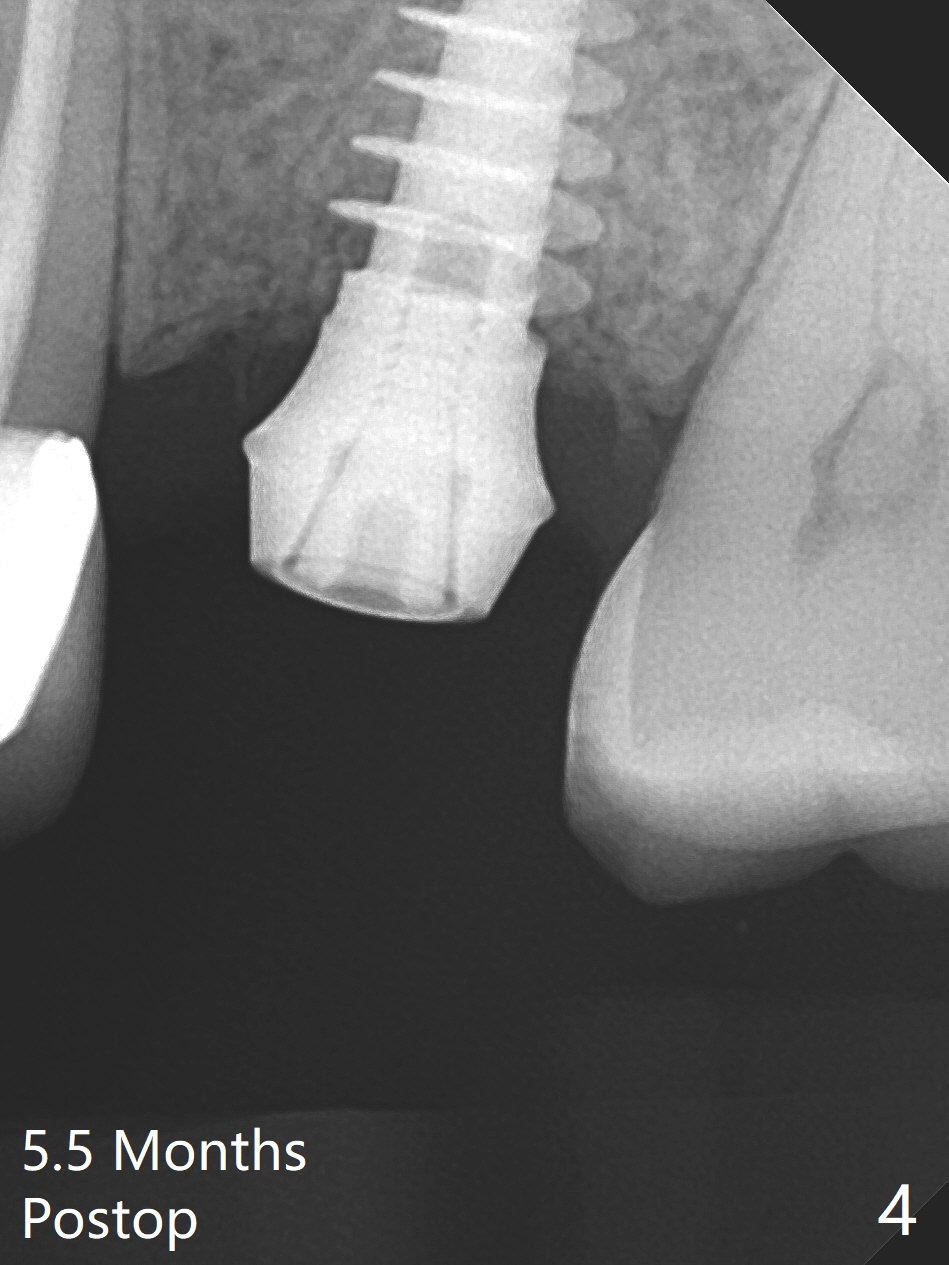

The ridge is wide at #14 11 months post socket preservation. Access and bone expansion (BEB) starts with Magic Split, followed by Magic Expanders 3.0, 3.8 and 4.3 mm from 8 to 9 mm for sinus lift. No bone is removed for osteotomy. Instead bone condensation occurs. After placement of a 4.5x11 mm dummy FC implant (Fig.1 with sinus lift (without bone graft)), a 5x9(2) mm Magicore (2 mm cuff) is placed with >55 Ncm with cuff margin at the gingival margin (Fig.2); a 5.5x3 mm solid abutment tries in. There is no occlusal clearance; trimming of the solid abutment will be needed. Later a healing screw is placed (Fig.3 *). There is no bone loss 5.5 months postop (Fig.4). A healing cap is placed without much tissue blanching. Instead a 5.5x3 mm solid abutment is placed; after height adjustment, impression is taken. A permanent crown is temporarily cemented 6 months postop (to rule out food impaction) and permanently re-cemented 7 months postop (Fig.5,6). CBCT taken 3-4 months post cementation shows that the implant threads are within the bone (Fig.7) and that the implant barely enters the sinus (Fig.8 *). That is significant since the patient has chronic sinusitis with thickened sinus membrane (Fig.9 *). The tooth #18 seems to have crazing line 10 months post cementation of the crown at #14 (overloading, Fig.10).